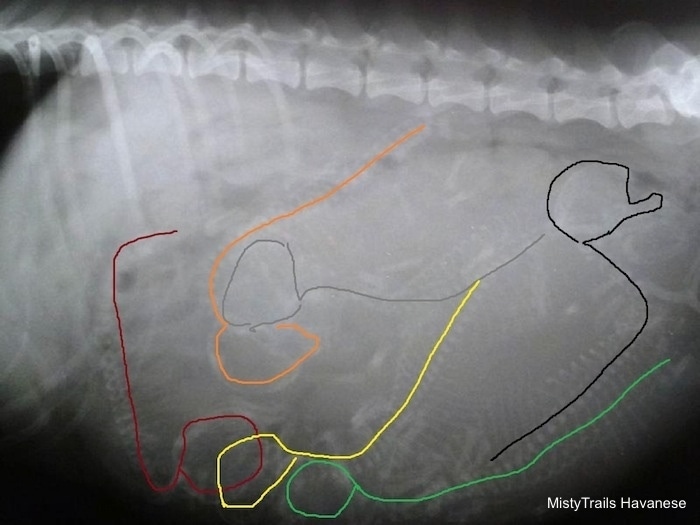

У беременных сук увеличение матки можно зафиксировать только на 21-й день беременности. С 21-го но 42-й день беременности можно видеть увеличенные, наполненные жидкостью рога матки. Скелеты плодов становятся рентгенонепрозрачными на 44-47-й день беременности или на 35 40-й день диэструса, а череп и позвоночник становятся видны раньше длинных костей и костей пальцев. Для постановки точного диагноза беременности нужно 2 дня (Сопсаппоп andRendano, 1983). Зубы плодов различают на 58 63-й день. Если основываться на дате первой вязки, то минерализацию скелета можно идентифицировать уже на 42-52-й день после вязки После 47-го дня беременности, когда скелеты плодов будут минерализованы настолько, чтобы стать рентгенонепрозрачными, но рентгеновским снимкам можно определить размер помета. Он зависит от многих факторов, но чаще всего у мелких пород в — будет 2- 4 щенка, у средних пород — 4 7, а у крупных собак от 6 до 10 щенков. Рентгенография позволяет точно подсчитать численность малого помета, но даже несмотря на се более высокую точность но сравнению с ультрасонографией, на рентгеновских снимках нс всегда возможно подсчитать количество щенков в больших пометах. Самый легкий путь определения размера помета — подсчет количества черепов и позвоночников на рентгеновских снимках (рис. 8 и 9).

С помощью рентгенографии можно подтвердить жизнеспособность плодов по отсутствию внутриматочных плодных MCuiKOB, наполненных газом, или деформации и изгиба частей скелета, что происходит после гибели плодов (рис 10).

Щенки щенков

Ниже приведены различные рентгенограммы беременных дам, которые вот-вот родятся. Некоторые из них обозначены позициями щенков, чтобы помочь вам лучше понять, как определять щенков.

Целесообразно сделать рентген плотины за день или два до родов. Это отличный инструмент не только, чтобы показать вам, сколько, но и размеры и позиции щенков.Этот рентген был сделан за три дня до рождения щенков.

Этот рентген был сделан за день до рождения щенков. Вы можете видеть одного щенка, участвующего в родовом канале. Она в течение 24 часов с момента доставки.

Рентгенс изображением трех щенков.

Рентген с изображением четырех щенков.

Если вы сделаете рентген в дни 55/56/57, то сможете увидеть головы, позвоночники, ребра и ноги.Сначала посчитайте головы, а затем найдите позвоночник, который будет идти с каждой головой. На этом рентгеновском снимке точно показаны шесть щенков одинакового размера, и ничего страшного. Там может быть семь щенков, с возможностью восьми. Смотрите рисунок ниже, чтобы помочь найти щенков

На этой картинке изображены щенки, которых можно увидеть наверняка.

Эта картина показывает тревожный исход. Один из щенков кажется мертвым и блокирует родовой канал.Кесарево сечение должно быть выполнено.